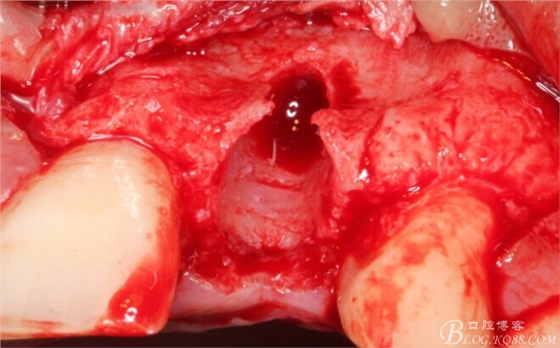

于是我果斷告知患者,手術(shù)失敗了,不能拖延,如不及時(shí)處理,炎癥繼續(xù)發(fā)展會(huì)很快波及鄰牙牙槽骨。患者接受我的建議。切開翻瓣,骨粉及生物膜消失了,骨吸收嚴(yán)重,幸運(yùn)的是,因?yàn)樘幚砑皶r(shí),鄰牙骨支持依然存在。

徹底掻刮。

有老師問我,為什么不在此時(shí)同期植骨同期植入植體?我的觀點(diǎn)是:不要一次做太多事情,做得越多風(fēng)險(xiǎn)越高。再說,此時(shí)軟組織不健康,沒有健康的軟組織如何能保證GBR的成功?所以,我僅放了一塊膠原蛋白就縫上了。